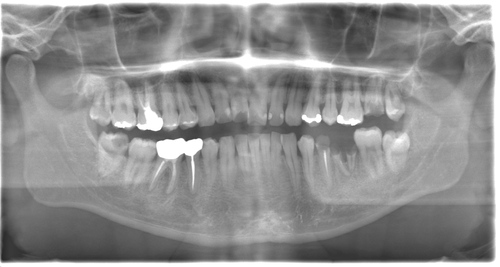

CASE 12

| 年齢・性別 | 29歳・女性 |

| 主訴 | 左上下親知らず抜きたい |

| 抜歯期間 | 30分 |

| 抜歯費用 | 約2,500円(保険内) 別途CT撮影で3,000円 (2022年7月現在) |

| 抜歯内容 | 左上下の親知らず抜歯 |

| 治療方針 |

初めに右下の奥歯が痛いとのことでご来院されました。 右下の親知らずと7番目の歯がカリエスになっていたため、まずは右下の親知らず抜歯と7番目の感染根管治療を行いました。左上下の親知らずもカリエスになっているため、今回抜歯を行いました。 |